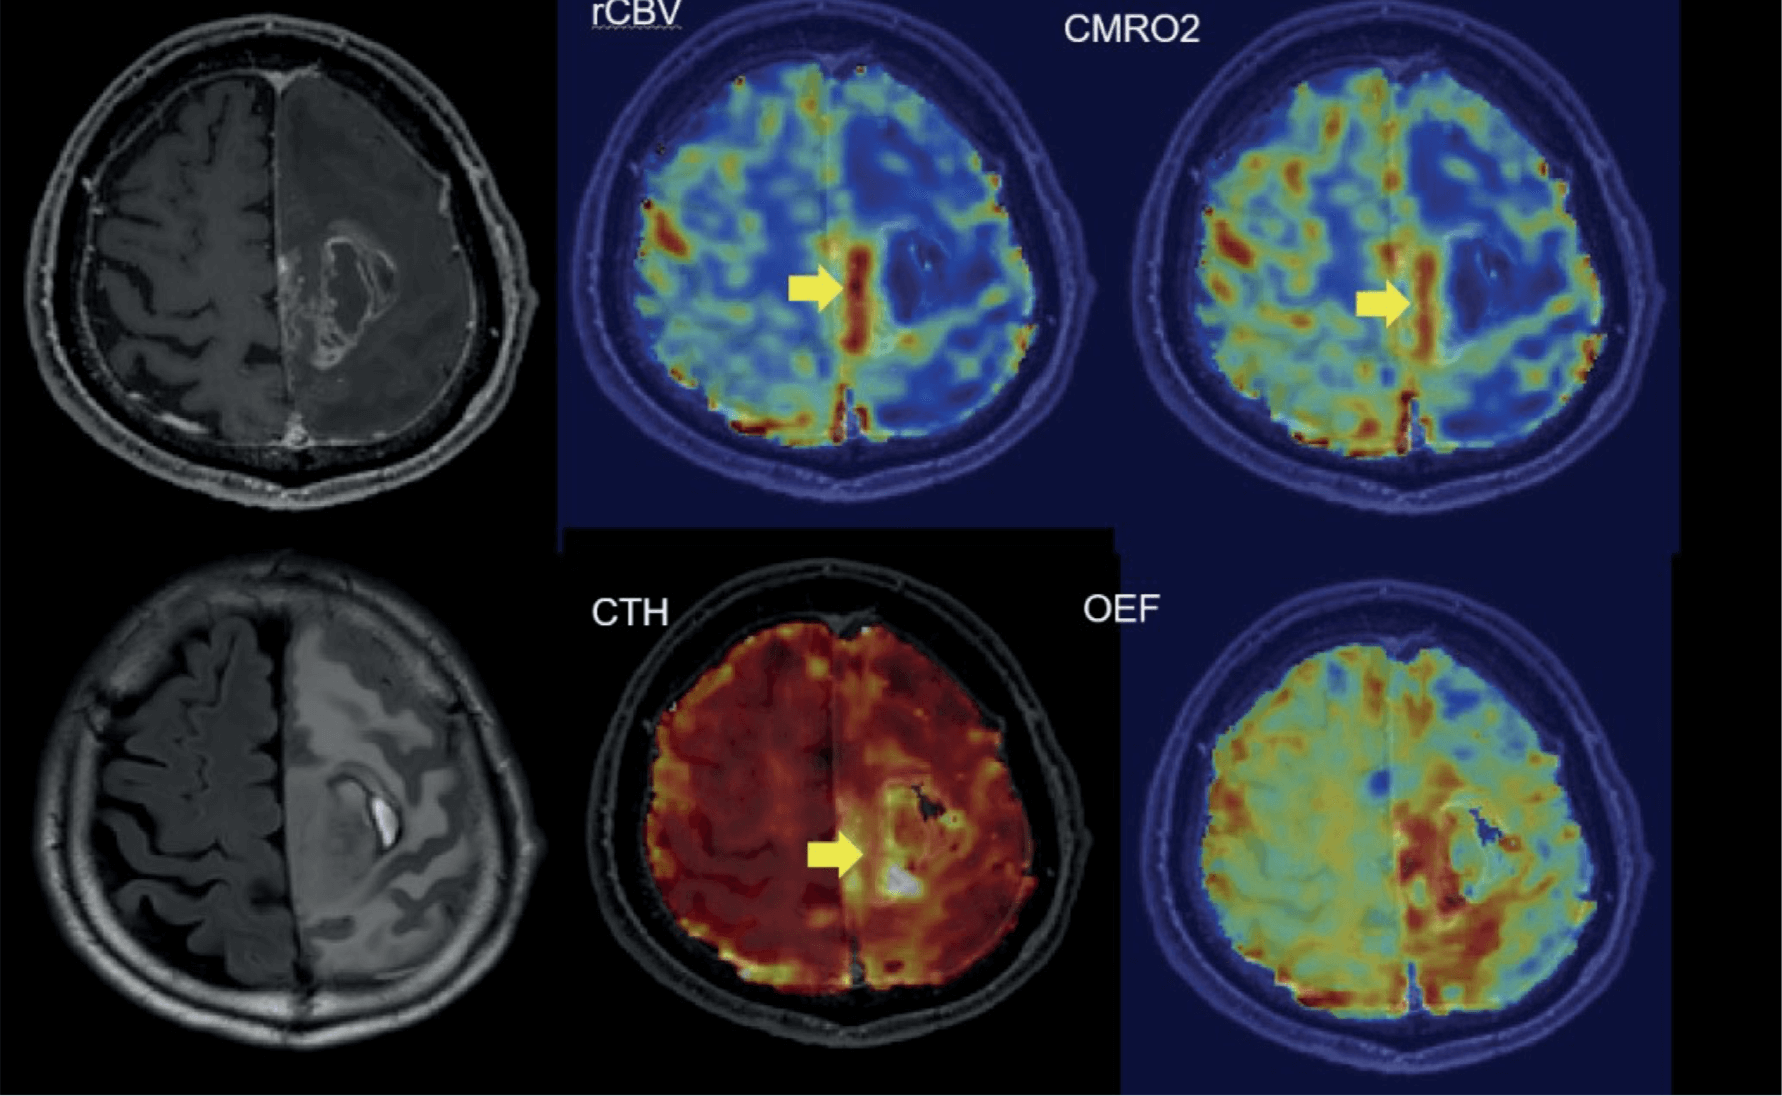

THE VASCULAR MODEL: A NEW STANDARD OF EVALUATION

The Vascular Model (VM) developed by Cercare Medical is a key component of all Stroke solutions.

Compared to traditional models, the VM offers:

- clearer visualization of hypoperfused areas,

- better correlation with final infarction,

- greater consistency with the patient's actual neurological deficits.

Metabolic Biomarkers

- OEF Fractional Oxygen Extraction Rate.

- CMRO₂ Metabolic Oxygen Consumption Rate.